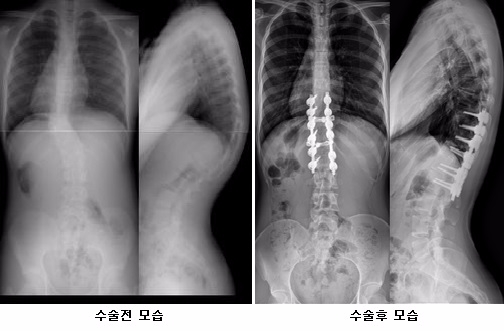

연구팀은 뼈가 휘는 정도를 뜻하는 만곡 각도가 10세 이하 그룹에서는 수술 전 평균 44도에서 수술 후 10.2도(76.8% 교정), 최종 추시 시 14.2도(67.7% 교정)로 호전을 보였고, 10세 이상 그룹에서는 수술 전 48.7도에서 수술 후 17.2도(64.7% 교정), 최종 추시 시 20.4도(58.1% 교정)로 호전되었다고 밝혔다.

후방 척주 절제술은 후방으로만 접근해서 수술하여 한꺼번에 척추 기형을 제거하는 방법으로 변형의 교정력이 높을 뿐만 아니라, 제거되는 기형의 병변을 조절하여 후만증과 측만증을 동시에 교정할 수 있는 우수한 수술 방법이다. 이 수술법은 상계백병원 척추센터에서 2002년 세계 최초로 도입하여 현재는 전 세계적으로 널리 사용되고 있는데, 이번 분석 결과로 ‘후방 도달 척주 절제술’의 우수성이 다시 한 번 입증되었다.